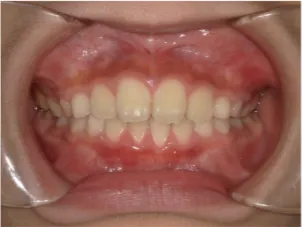

治療後⑤中3:咬合治療終了 マルチブラケット法の期間は9か月